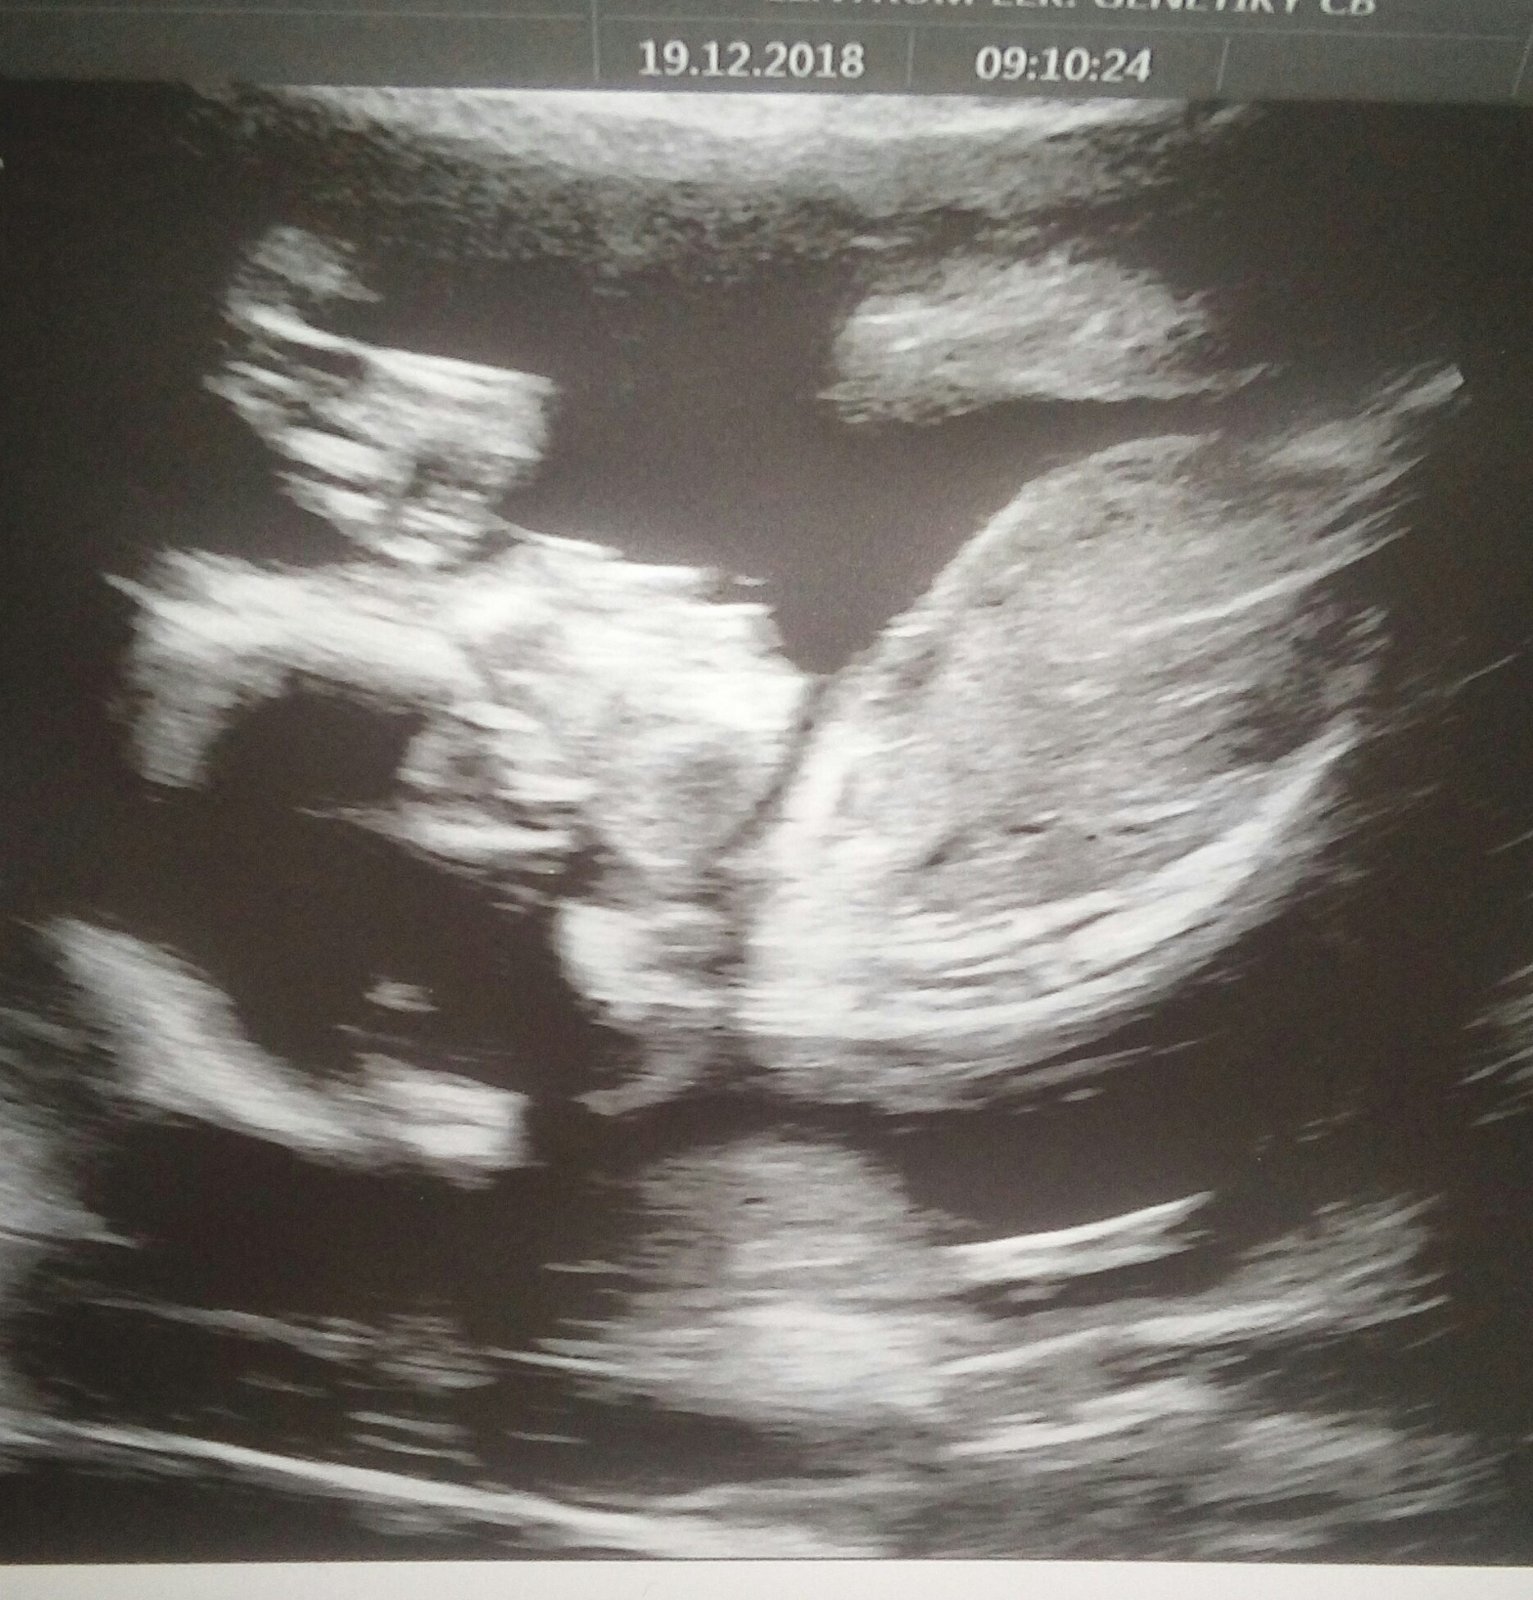

Přikládám foto ultrazvuku holčičky v 16tt pro ostatní maminky pro porovnani, je to zaber zespodu jakoby na prdku s roztazenyma nozkama 😉.

@kristyna14092013 holčička. pohlavní hrbolek je souběžně s osou páteře. kdydy výrazně čněl nahoru, je to kluk 🙂